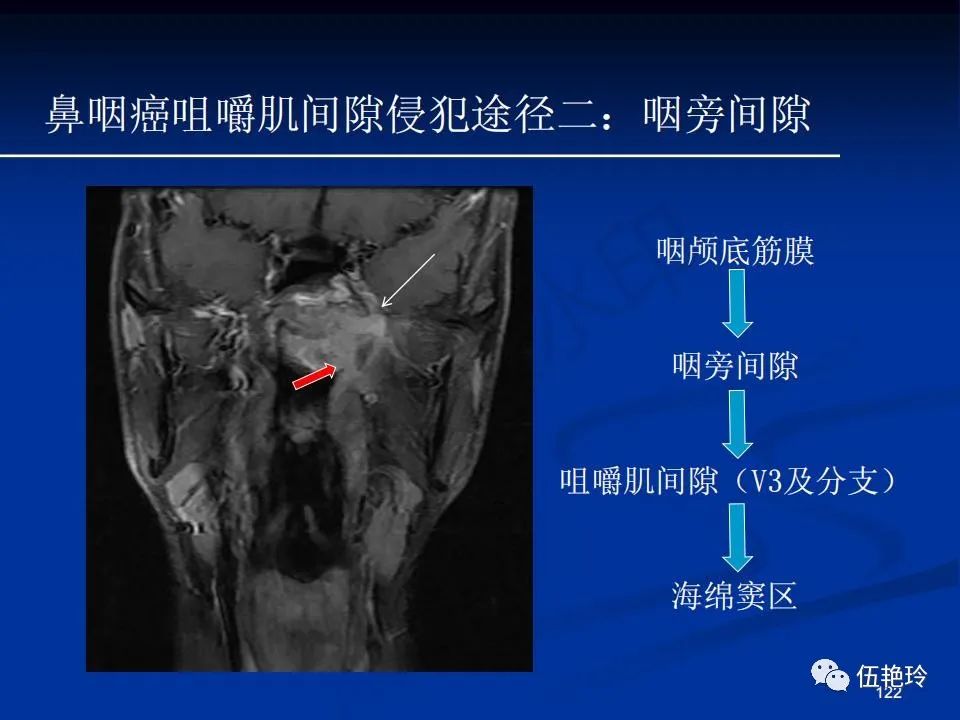

颞下窝与咀嚼肌间隙

2.31 向上颅内:①鼻咽顶壁→破裂孔(岩尖、斜坡)→蝶窦、海绵窦;②鼻咽顶壁→蝶骨基底部→蝶窦、海绵窦;③鼻咽侧壁→茎突前间隙→蝶骨大翼(卵圆孔)→海绵窦;④鼻咽侧壁→茎突前间隙→翼腭窝→ 颞下窝;⑤鼻咽前壁→鼻腔→翼突、翼腭窝→眶下裂→眶尖→海绵窦;⑥鼻咽前壁→鼻腔→上颌窦、筛窦;